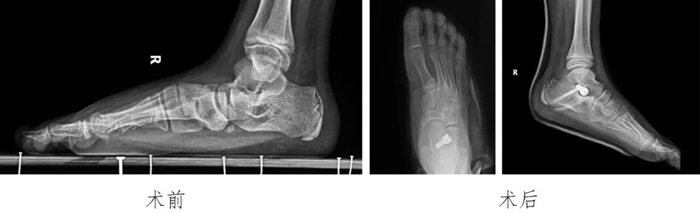

4?青少年扁平足:

通過跗骨竇區(qū)微創(chuàng)小切口放置距下關(guān)節(jié)制動器治療青少年的扁平足,患兒術(shù)后足弓恢復(fù),得到患兒家長的認(rèn)可。